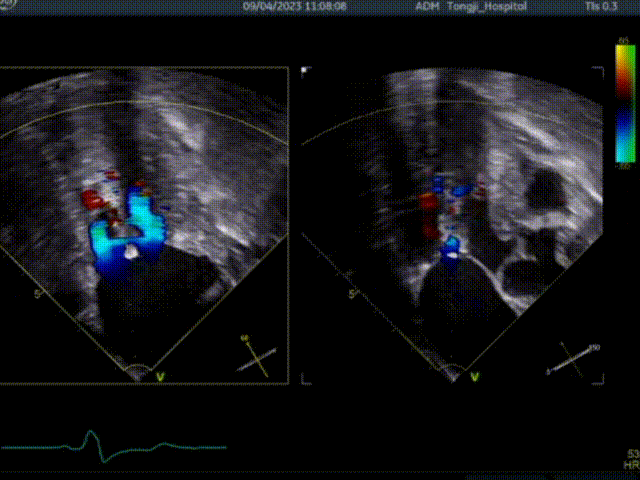

术前超声TEE检查结论:

1. 左室非对称性肥厚,左室流出道梗阻,二尖瓣重度关团不全;

2. 二尖期后叶脱垂;

3. 卵圆孔未闭(极细缝隙)。

患者术前大量反流,前叶SAM征,室间隔增厚最厚处13mm